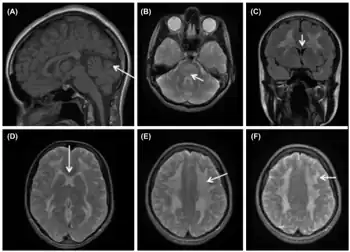

Like other mitochrondrial diseases, MNGIE is a multisystem disorder.[5] MNGIE primarily affects the gastrointestinal and neurological systems. Gastrointestinal symptoms may include gastrointestinal dysmotility, due to inefficient peristalsis, which may result in pseudo-obstruction and cause malabsorption of nutrients.[1][4] Additionally, gastrointestinal symptoms such as borborygmi, early satiety, diarrhea, constipation, gastroparesis, nausea, vomiting, weight loss, and diverticulitis may be present in MNGIE patients.[1] Neurological symptoms may include diffuse leukoencephalopathy, peripheral neuropathy, and myopathy.[1] Ocular symptoms may include retinal degeneration, ophthalmoplegia, and ptosis.[1][4] Those with MNGIE are often thin and experience continuous weight loss. The characteristic thinness of MNGIE patients is caused by multiple factors including inadequate caloric intake due to gastrointestinal symptoms and discomfort, malabsorption of food from bacterial overgrowth due to decreased motility, as well as an increased metabolic demand due to inefficient production of ATP by the mitochondria.

While the disease manifests early in life in most cases, diagnosis of the disease is often quite delayed.[1][3][4] The symptoms that affected patients present vary, but the most common presenting symptoms are gastrointestinal issues such as nausea, vomiting, abdominal pain, and diarrhea, and neurologic or ocular symptoms such as hearing loss, weakness, and peripheral neuropathy.[3] These gastrointestinal symptoms cause patients with MNGIE to be very thin and experience persistent weight loss and this often leads to MNGIE being misdiagnosed as an eating disorder.[1] These symptoms without presentation of disordered eating and warped body image warrant further investigation into the possibility of MNGIE as a diagnosis.[1] Presentation of these symptoms and lack of disordered eating are not enough for a diagnosis. Radiologic studies showing hypoperistalsis, large atonic stomach, dilated duodenum, diverticula, and white matter changes are required to confirm the diagnosis.[3] Elevated blood and urine nucleoside levels are also indicative of MNGIE syndrome.[1] Abnormal nerve conduction as well as analysis of mitochondria from liver, intestines, muscle, and nerve tissue can also be used to support the diagnosis.[1][3]